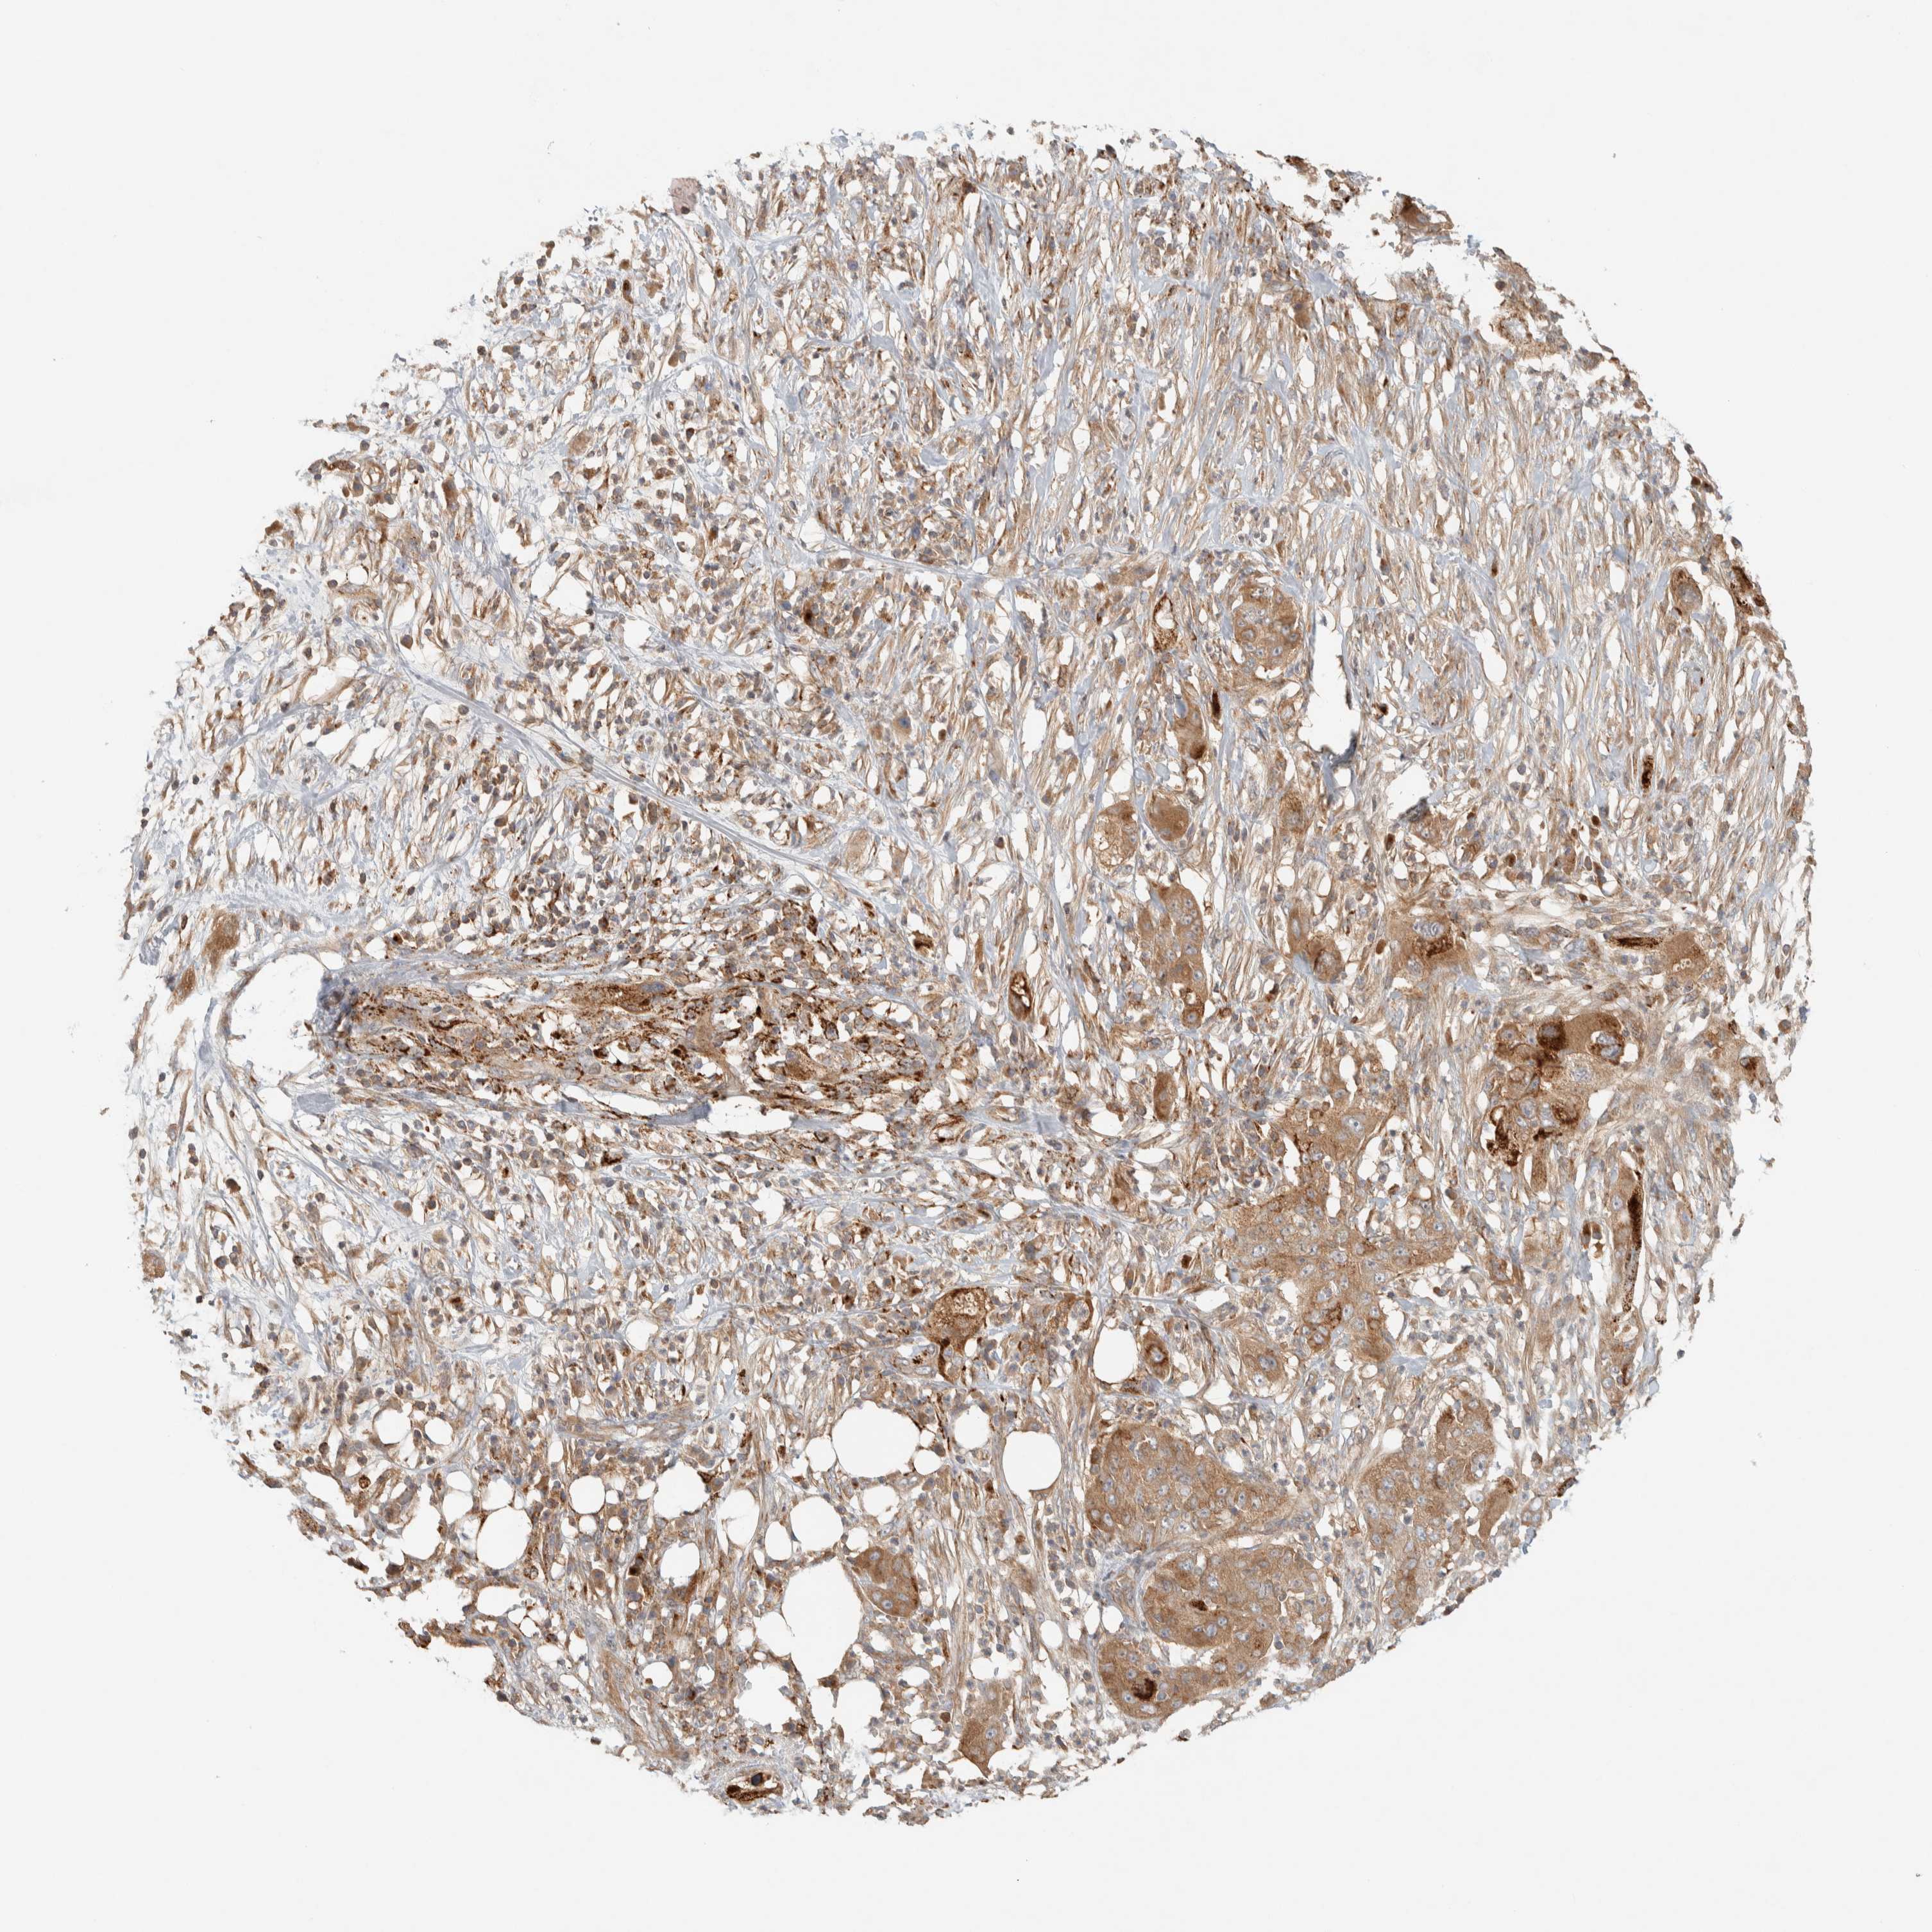

PANCREATIC CANCER - Protein expressioni

A mouse-over function shows sample information and annotation data. Click on an image to view it in a full screen mode. Samples can be filtered based on level of antibody staining by selecting one or several of the following categories: high, medium, low and not detected. The assay and annotation is described here.

Note that samples used for immunohistochemistry by the Human Protein Atlas do not correspond to samples in the TCGA dataset.

Antibody stainingi

Antibody staining in the annotated cell types in the current human tissue is reported as not detected, low, medium, or high, based on conventional immunohistochemistry profiling in selected tissues. This score is based on the combination of the staining intensity and fraction of stained cells.

Each image is clickable and will lead to virtual microscopy that enables deeper exploration of all samples and also displays staining intensity scores, fraction scores and subcellular localization as well as patient and tissue information for each sample.

Antibody HPA023915

Antibody HPA030426

Staining

High

Medium

Low

Not detected

Intensity

Strong

Moderate

Weak

Negative

Quantity

>75%

75%-25%

<25%

None

Location

Nuclear

Cytoplasmic/membranous

Cytoplasmic/membranous,nuclear

Adenocarcinoma, NOS